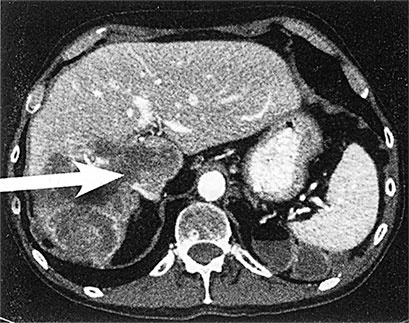

Пролистнем следующие несколько тысячелетий, в течение которых рак продолжал поражать тела молодых и стариков. Одним из проницательных и наблюдательных врачей во времена Античности был римский физиолог, хирург и писатель Гален. Он предложил теорию заболеваний в то время, когда такие дисциплины, как анатомия, патофизиология и фармакология, находились в зачаточном состоянии. Медик II века н. э. Гален внес серьезный вклад в понимание патологии по Гиппократу. Гиппократ, как вы помните из школьного курса биологии, считается отцом медицины и разработчиком многих теорий в области здоровья (Афины, примерно 400 г. до н. э.). Физиологические и философские наблюдения Гиппократа легли в основу современной медицины. Современные медики считают его первым человеком, который поверил в то, что заболевания вызываются естественными причинами, а не воздействием колдовства или высших сил. Более того, он впервые зафиксировал различия между доброкачественными и злокачественными опухолями. Для описания опухолей разных частей тела, перерастающих в язвы, Гиппократ ввел понятие karkinos (греч. «краб»). Не очень понятно, почему раковая опухоль похожа на краба, но образ подошел. Гиппократ видел и описывал опухоли, вокруг которых были пучки воспаленных кровеносных сосудов, что и навело на мысль о крабе, закопавшемся в песок и выставившем конечности наружу. То, что Гиппократ описывал раковую опухоль как «похожую на краба», явно свидетельствует о том, что он не знал о видах рака, которые нельзя увидеть невооруженным взглядом. Чаще всего он видел большие опухоли на поверхности тела или близко к поверхности, такие как опухоли молочных желез, кожи, шеи и языка. Идеи Гиппократа в области здоровья и болезней позволили его последователям, таким как Гален, развивать их и ставить эксперименты. Некоторые эти эксперименты помогли дать точное определение рака. Гален описал его как неуправляемую и безжалостную часть тела. По его мнению, к раку приводил излишек обычной «черной желчи», которую невозможно убрать. Черная желчь поражала все тело, а опухоли отражали силу и упорство этого распространяющегося злокачественного состояния. Попытки вырезать такие опухоли не приведут к успеху, считал античный врач, так как черная желчь не только заполнит рану, но и приведет к развитию еще одной опухоли. У Галена не было изощренных терминов и инструментов вроде современных микроскопов и установок секвенирования генома, но он точно описал системную природу рака и его способности расти, давать метастазы и восстанавливаться. Многие идеи Галена сохранили свою актуальность до Возрождения, а студенты-медики продолжали изучать его труды до XIX века. Потом, когда патофизиологи XIX века направили микроскопы на внедрившиеся клеточные массы, они поняли жестокую шутку, которая и определяет природу рака: это избыток собственных клеток, а не черной желчи. Но эти клетки похожи на черную желчь, так как ведут себя как мятежники, которые рушат границы и грабят остальные клетки. Раковые клетки похожи не только аномальной формой, но и безудержной пролиферацией – бесконтрольным клеточным ростом. Сидхарта Мукерджи красиво описал этот процесс в книге «Король всех недугов», которая описывает место рака в истории человечества. На молекулярном уровне рак появляется после мутации генов конкретной клетки. Мощные генетические сигналы нормальных клеток указывают, когда и как клетке делиться. Некоторые гены активизируют размножение клеток, работая как педаль газа. Другие работают как молекулярные тормоза, останавливая рост. Это объясняет, в частности, почему, например, когда заживает царапина на коже, клетки, задействованные в заживлении, «знают», когда нужно останавливать развитие новых клеток, так чтобы не оставить вас с опухолью из новой кожи. Но в раковой клетке нет этого отточенного баланса между активным ростом и неактивностью. Светофор, который управляет ростом клеток, не работает или слишком часто дает зеленый свет. Клетки, соответственно, остаются без регулирования и не знают, когда прекращать рост. Но такой взгляд на рак на молекулярном уровне не является единственным полезным инструментом в подборе лечения. Для меня рак (рис. 4) выглядит примерно так: ![]() А. Печень человека с метастазами рака толстой кишки ![]() Б. Аксиальная компьютерная томография, показывающая наличие метастазов рака в печени ![]() В. Рак в лимфоузле под микроскопом Вот мы видим А – печень с раком толстой кишки, что правильнее назвать «метастазы рака толстой кишки в печень». Рак переместился, метастазировал, из толстой кишки в печень, что подтверждается белыми образованиями на снимке. Б – томограмма другой печени, пораженной раком толстой кишки («метастазы рака толстой кишки в печень»). Обратите внимание на пять круглых темных образований в левой части изображения. И В – изображение рака толстой кишки в лимфоузле под микроскопом («метастазы рака толстой кишки в лимфоузел»). Пояснение: «рак толстой кишки», который метастазировал в легкие, не будет называться «рак легких». Это все еще рак толстой кишки и выглядит он как рак толстой кишки. Рак – это взаимодействие клетки, лишенной контроля роста, с окружающей средой. Для понимания рака важнее обратить внимание на то, что это не только неконтролируемое деление клеток и их распространение. Важнее другая характеристика – способность изменяться со временем. Хотя люди часто представляют себе рак как сошедшую с ума машину для копирования клеток, не вносящую изменений, в действительности он гибче и динамичнее. Каждый раз, когда появляется новое поколение злокачественных клеток, в них появляются новые мутации – которые еще сильнее меняют гены, отвечающие за рост клетки. Хуже того: в опухоли после химиотерапии могут остаться клетки, резистентные к лекарственным средствам. Другими словами, так же, как после применения антибиотиков появляются резистентные бактерии, противораковые средства могут стимулировать появление резистентных раковых клеток. Но вновь отстранимся от молекулярной точки зрения на рак. Как видно, эволюция влияет на проявления рака, но не на генетику. Да, за злокачественные опухоли отвечают разные гены, но внешний вид получается одинаковым. Да, могут существовать 50 различных молекулярных путей развития того или иного новообразования, например, рака молочной железы, толстой кишки, легких, мозга или простаты, но в итоге результат и способ действия оказываются одинаковыми. Если показать гистологу десять образцов рака молочной железы от разных пациентов, то молекулярная основа во всех случаях будет разной, но под микроскопом все будет выглядеть как рак молочной железы. Аналогично наблюдается удивительное сходство между видом клеток рака молочной железы и клеток рака любого другого органа, потому что у злокачественных клеток много общего во внешнем виде и поведении. Это – важнейший момент в понимании рака. Ученые долго изучали молекулярные дефекты, ведущие к раку, но не сам его вид. Описание от Национального института рака (стр. 49) составляет только часть общей картины. Рак – это не генетическое заболевание. Скорее это болезнь, при которой клетки начинают выглядеть и вести себя определенным способом, используя для этого генные мутации. И если при разработке новых методов лечения будет найден способ блокирования одного молекулярного пути, то это не означает, что рак не найдет другого (что, к сожалению, он обычно успешно проделывает). |